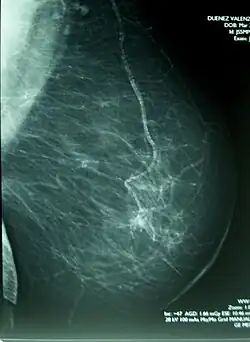

Mamograf (někdy používáno i mammograf, z lat. mamma – mléčná žláza savců, řec. graf – popisovat) je lékařské diagnostické zařízení, sloužící k diagnostice a prevenci nádorových onemocnění ženského prsu, tzv. mamografii. Mamograf pracuje na principu denzitometrie, tedy vyhodnocení změn v hustotě tkáně, prozařované relativně měkkým rentgenovým (X) zářením s energií 25–30 keV. Oblasti se zvýšenou hustotou a nehomogenitami jsou specifické pro nádorový proces. Pro zvýšení citlivosti metody se vyšetřovaná tkáň stlačuje na vrstvu cca 7–10 cm pomocí speciálních kompresních desek, které jsou součástí zařízení. Metoda využívá odlišosti činitele zeslabení pro zdravou tkáň prsu (která je z hlediska činitele zeslabení téměř homogenní) a pro kalcifikace, doprovázející léze.

Při běžném vyšetření se provádí snímkování v kraniokaudální projekci (CC), tedy shora dolů a v šikmé mediolaterální projekci (MLO) pro oba prsy. V případě potřeby přesnějšího vyšetření se provádí snímkování s bodovou kompresí případně další speciální druhy snímků (mediolaterální ML či lateromediální LM, tangenciální, mediálně nebo laterálně rozšířená).